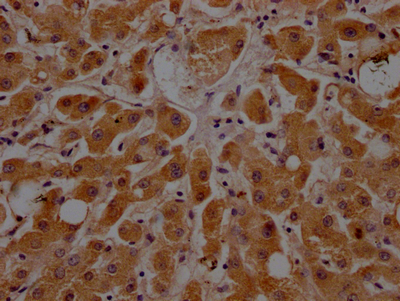

IHC image of CSB-RA925915A0HU diluted at 1:100 and staining in paraffin-embedded human liver tissue performed on a Leica BondTM system. After dewaxing and hydration, antigen retrieval was mediated by high pressure in a citrate buffer (pH 6.0). Section was blocked with 10% normal goat serum 30min at RT. Then primary antibody (1% BSA) was incubated at 4℃ overnight. The primary is detected by a Goat anti-rabbit IgG polymer labeled by HRP and visualized using 0.05% DAB.